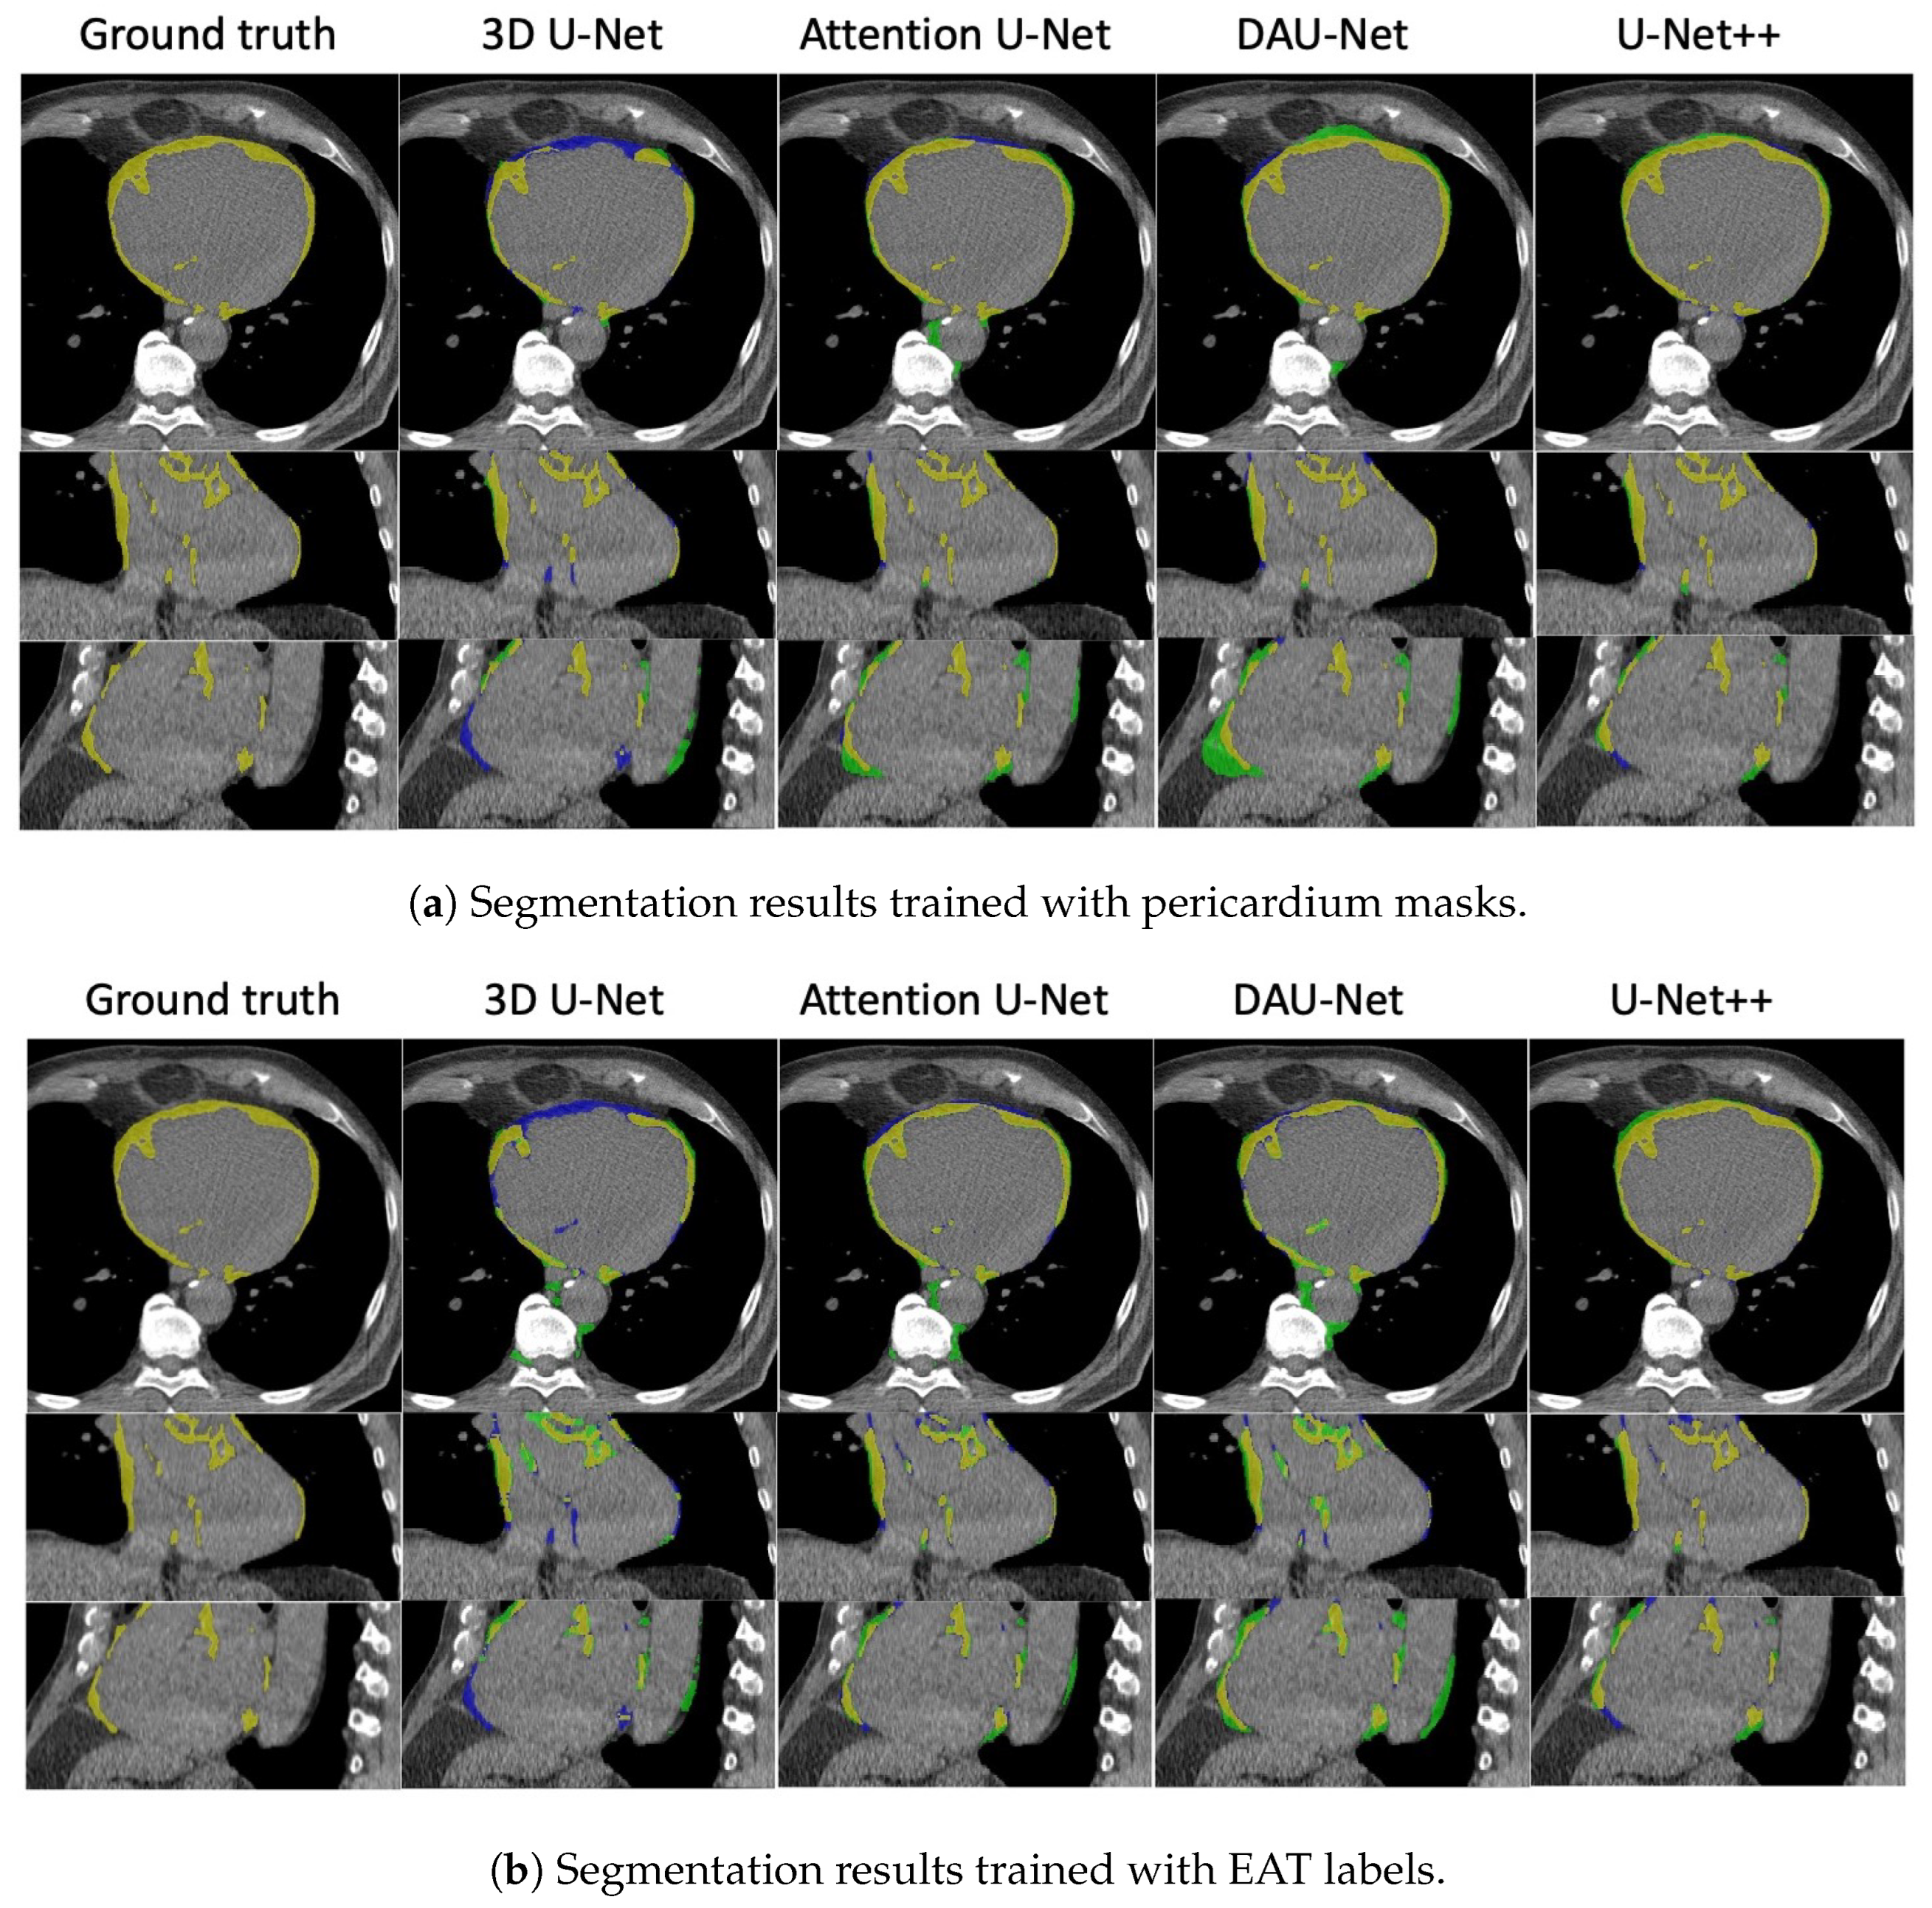

The comparisons between all models—3D U-Net, 3D attention U-Net, DAU-Net, and U-Net++—are demonstrated using 2D visualization in axial, coronal, and sagittal views in Figure 6a (models trained with pericardium masks) and Figure 6b (models trained with EAT labels). The corresponding errors are green for false positives and blue for false negatives. From the errors, we see that most of the mistakes were the false positive pixels (in green). In CT, most of the green pixels were the mediastinal fat located outside of the pericardium, but were similar to the EAT visually. Compared to the models trained with pericardium masks, models trained with EAT had more false negative pixels inside the pericardium.

Figure 6.

Visualization of segmentation results. The first column shows the ground truth, and the other columns show predictions from 3D U-Net, attention U-Net, DAU-Net, and U-Net++. The first row shows the segmentation in the axial view, the second row is for the coronal view, and the third row is for the sagittal view. In the segmentation results, the true positive is highlighted in yellow, the false positive is highlighted in green, and the false negative is highlighted in blue.